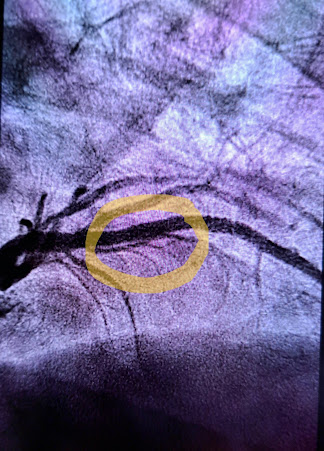

It's a nifty little thing that sticks (somewhat) discretely to one's chest, monitoring every heart beat and sending a report via a cell phone to the monitoring company. My instructions were to press a button on the accompanying cell phone any time I felt like my heart was beating rapidly for no obvious reason.

Again, so much more could be said, but it's not really my story to tell. I'm just glad Greg finally got in to see a cardiologist after much much too long of "feeling tired".